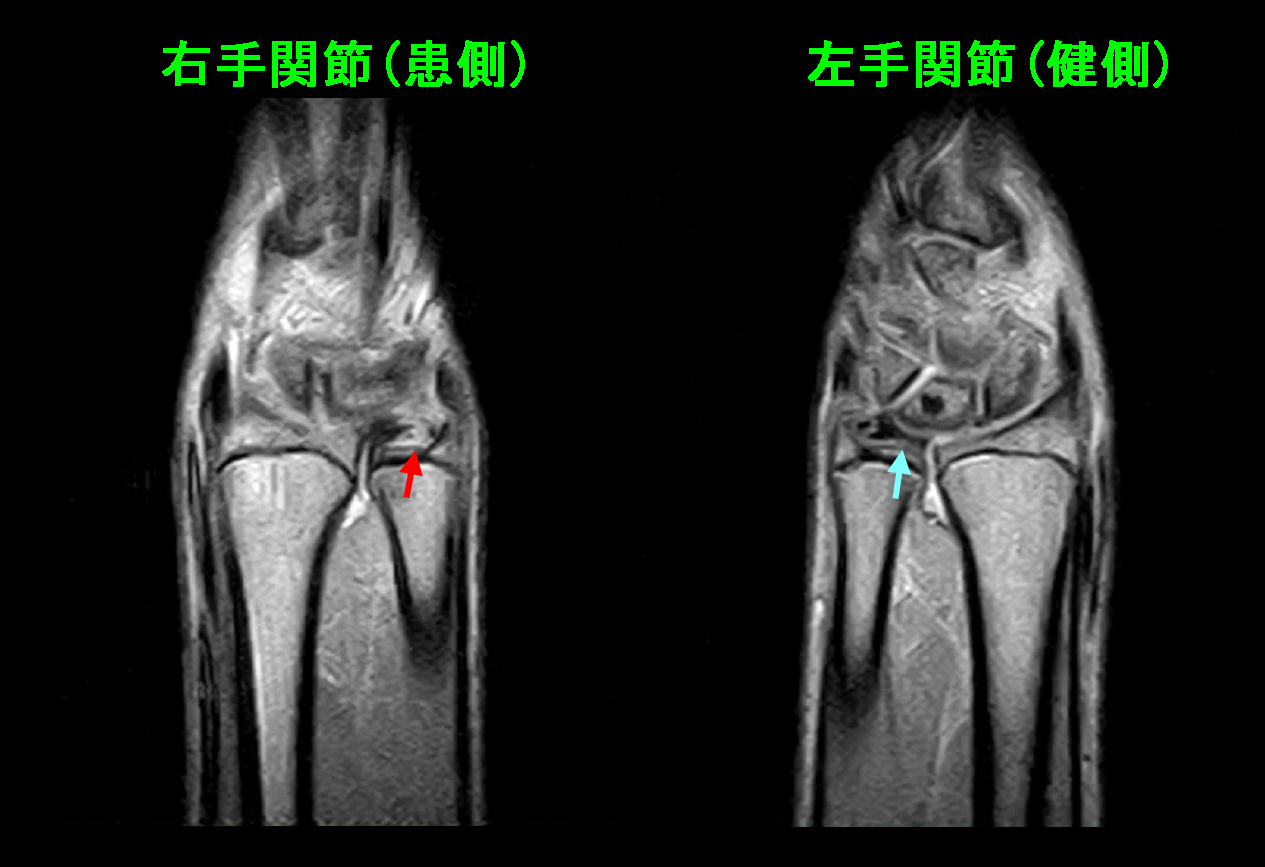

24才女 MR1.jpg

MRI検査では、三角線維軟骨は本来尺骨に密着していますが(右手関節・青矢印)、左の三角線維軟骨は尺骨から剥離し、同部位が白くなっています(赤矢印)。鎮痛剤とプレドニゾロンを1日2回の服用で1週間処方し、それで症状は軽減しました。